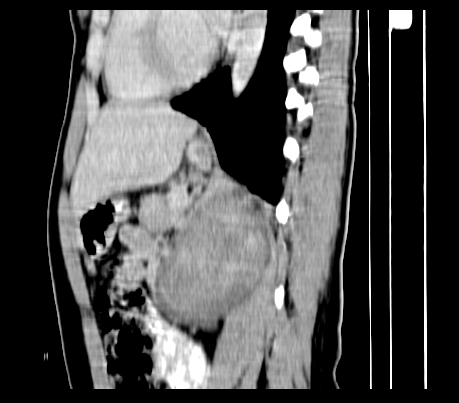

标题: CT23915:女 20岁 全身长疙瘩三年 今日多体位查 看看吧 [打印本页]

标题: CT23915:女 20岁 全身长疙瘩三年 今日多体位查 看看吧

重建